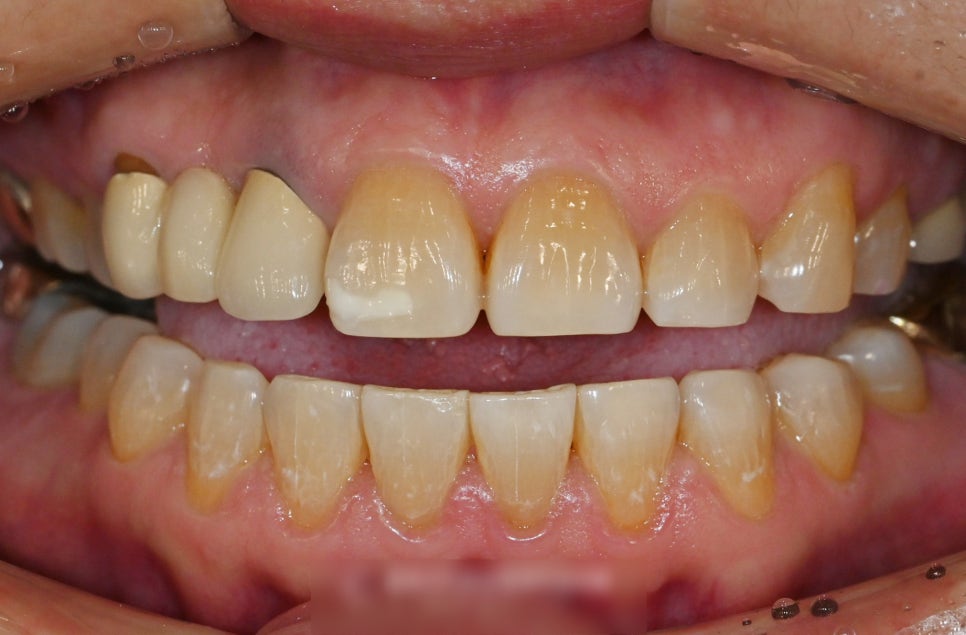

이와 같이 아래 앞니 사이 벌어짐은

말할 때, 밥 먹을 때 잘 보입니다.

살짝 다문다 하더라도

이와 같이 형성된 공간을 찾을 수 있습니다.

간격이 어느 정도 있는 편이라

눈에 크게 띌 수밖에 없는데요.

전반적으로 봤을 때,

전체 교합은 괜찮습니다.

부분교정을 통해 개선해볼 수 있습니다.

하악 전치부의 간격에 의하여

Space가 눈에 띄게 도드라집니다.

특히 41번과 42번에서의 간격이

넓은 편이었기에 진행되는 과정을 파악해

기간을 결정해야 될 것으로 사료됩니다.